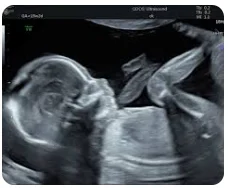

2. Mid-Trimester Anomaly Scan By Dr. Ekta Mishra

Join Dr. Ekta Mishra as she explains the crucial aspects of mid-trimester anomaly scans, focusing on identifying GI anomalies and skeletal abnormalities that are essential for early diagnosis.

• Grading echogenic bowel and its link to aneuploidies.

• How to spot abdominal cysts using imaging.

• Importance of timely intervention in fetal health.